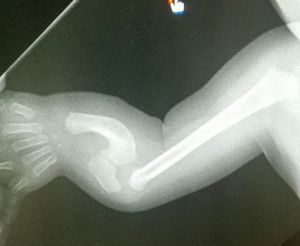

What is your diagnosis?

Xray

Children